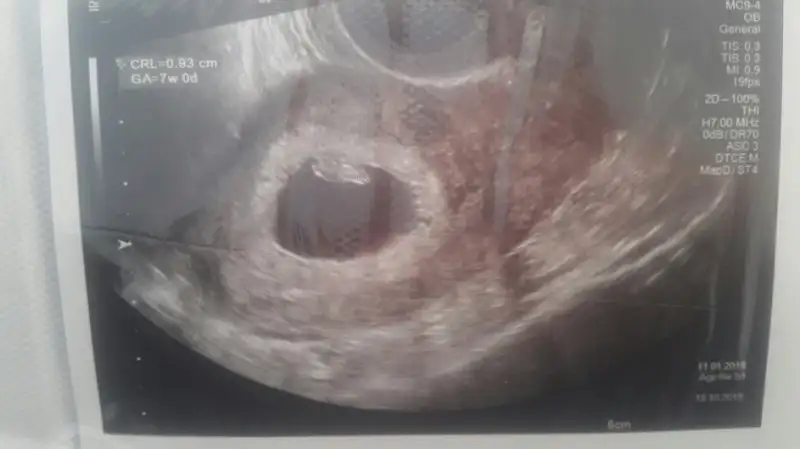

dün doktora gittik çok şükür herşey yolundaydı, hatta ufak bir hareket bile çekti bizim minik. 3 hafta sonra 2li için çağırdı doktorumuz.

Teoriye göre cinsiyet tahmini alabilir miyim ben de sizden :emir_bebek::)

• 2018-03-17 18.01.15.webp

2018-03-17 18.01.15.webp

11 KB · Görüntüleme: 76

• 2018-03-17 18.00.37.webp

2018-03-17 18.00.37.webp

9,5 KB · Görüntüleme: 77

Erkek diyorum :) 1 aya artik tum derdimiz cinsiyet olur insallah topikce :) netlesti mi netlesmedi mi heyecan yapalim :)